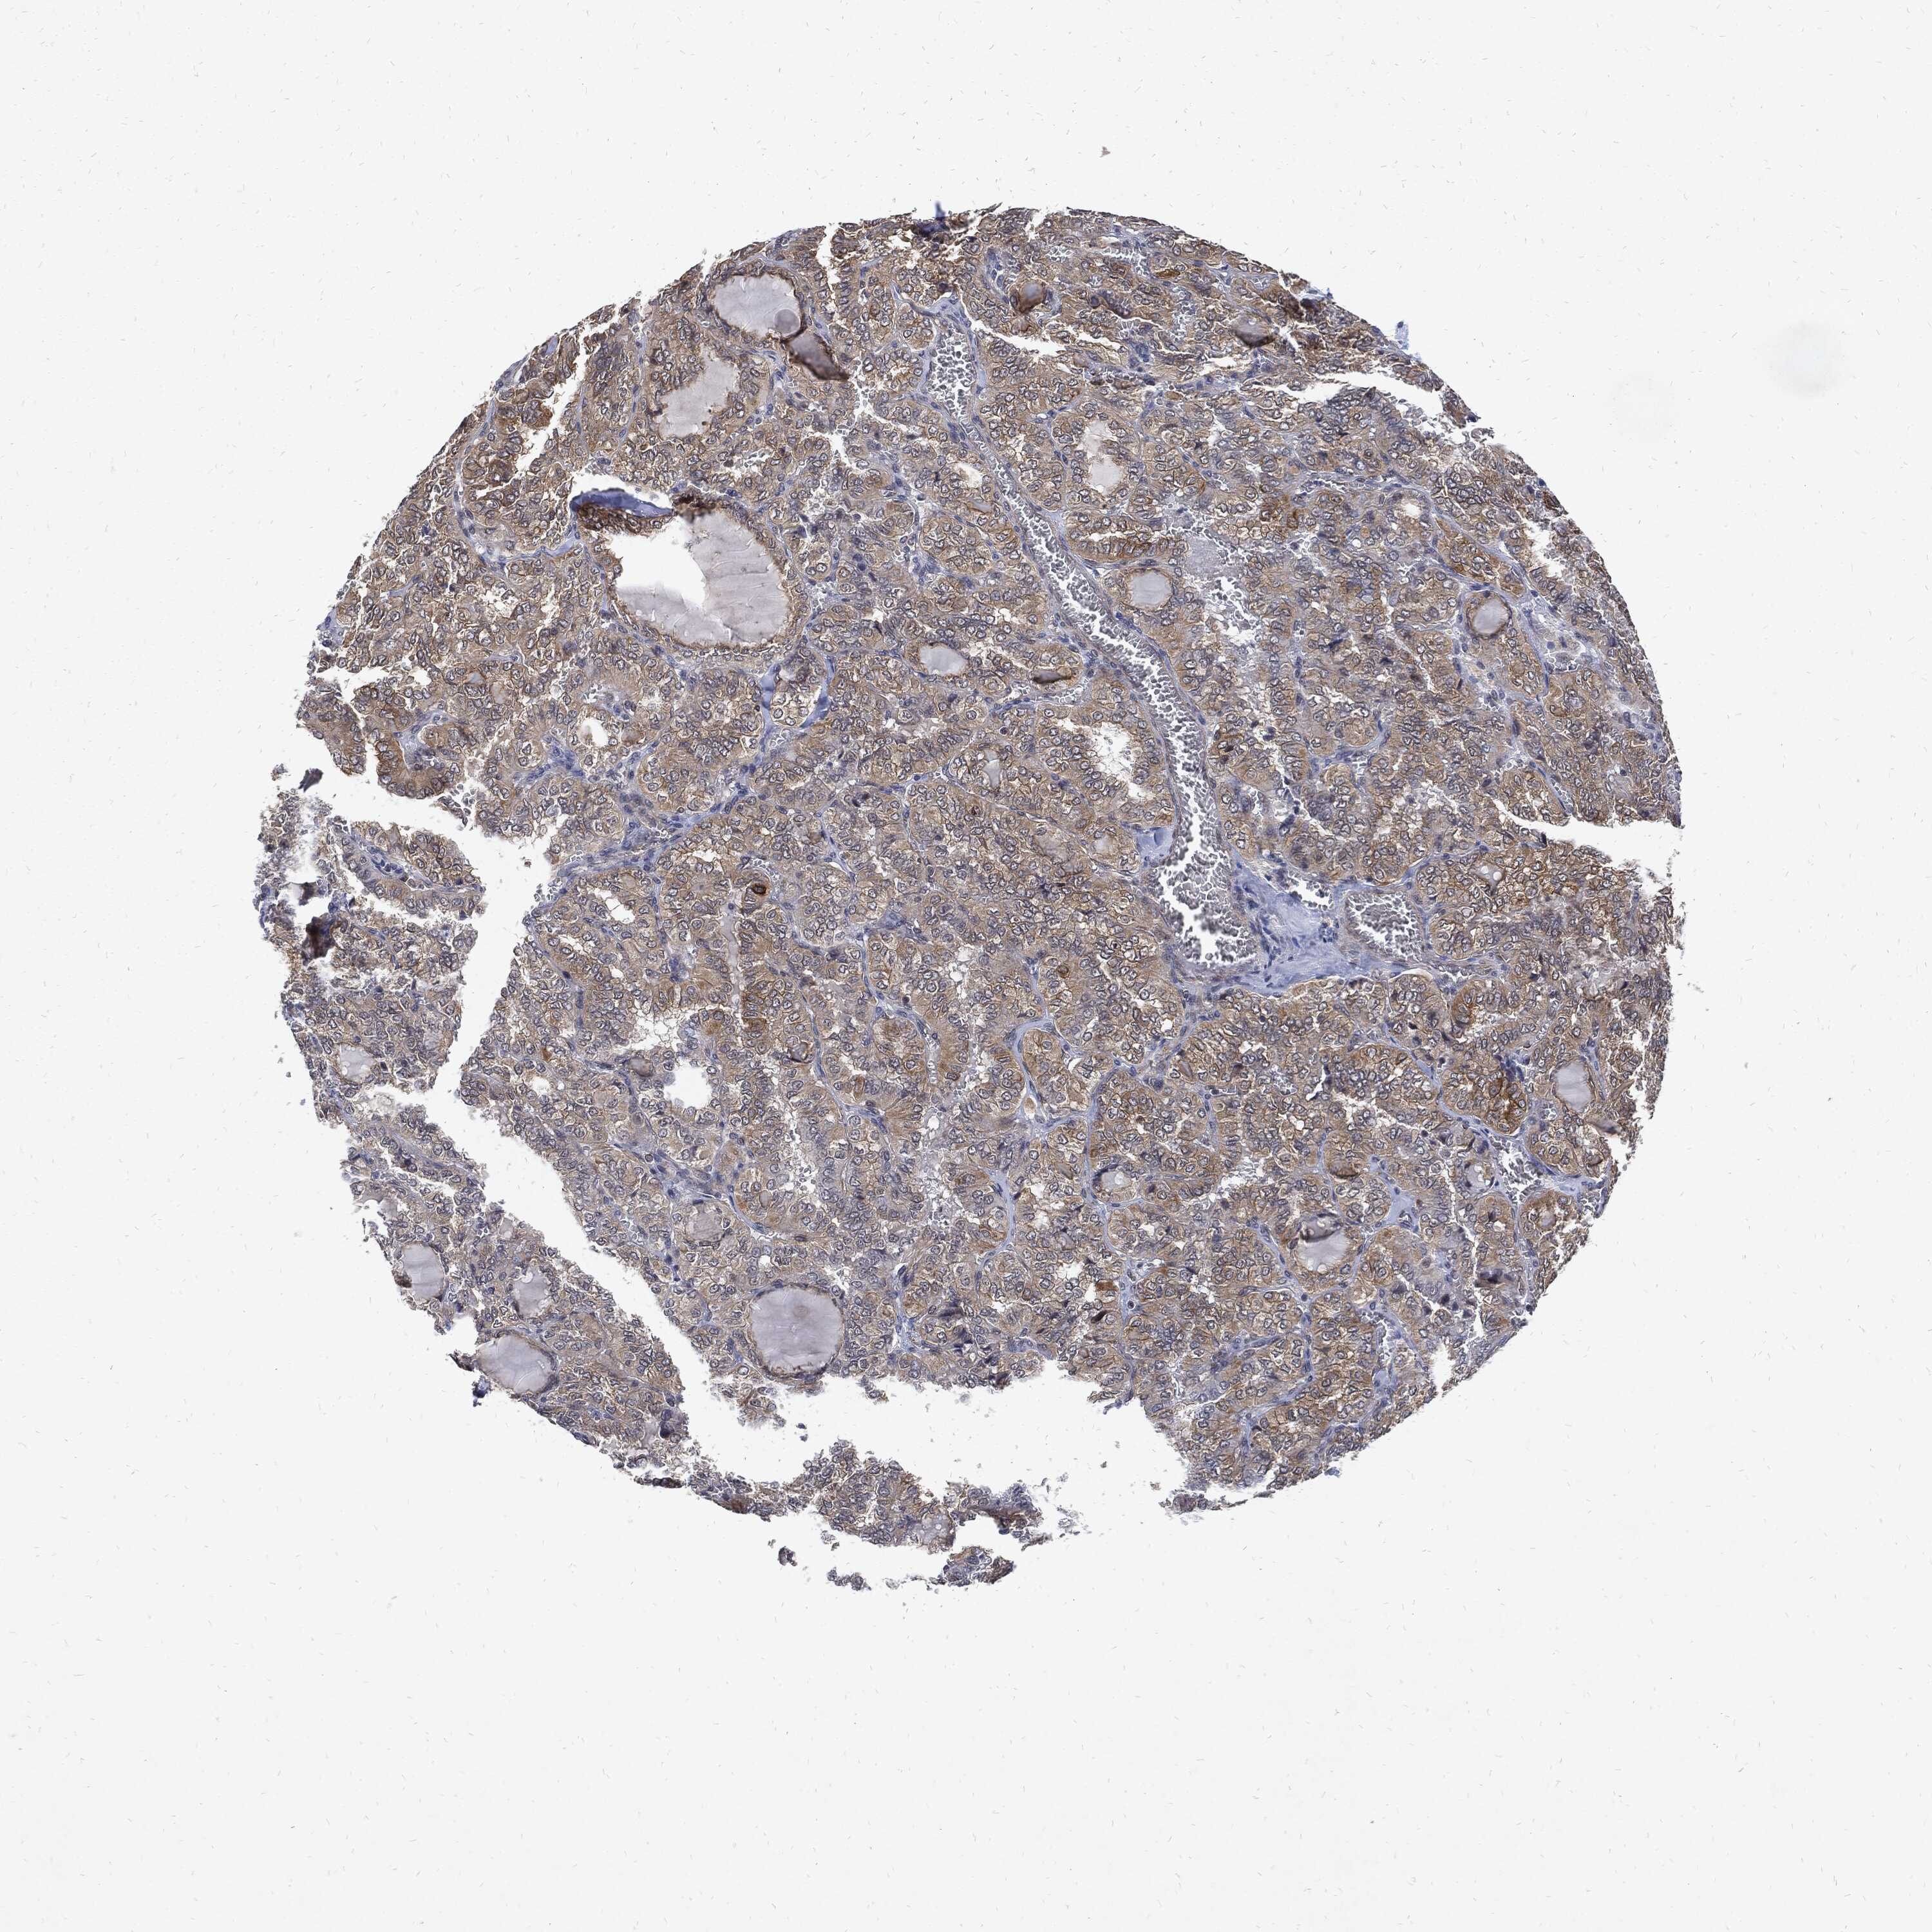

THYROID CANCER - Protein expressioni

A mouse-over function shows sample information and annotation data. Click on an image to view it in a full screen mode. Samples can be filtered based on level of antibody staining by selecting one or several of the following categories: high, medium, low and not detected. The assay and annotation is described here.

Note that samples used for immunohistochemistry by the Human Protein Atlas do not correspond to samples in the TCGA dataset.

Antibody stainingi

Antibody staining in the annotated cell types in the current human tissue is reported as not detected, low, medium, or high, based on conventional immunohistochemistry profiling in selected tissues. This score is based on the combination of the staining intensity and fraction of stained cells.

Each image is clickable and will lead to virtual microscopy that enables deeper exploration of all samples and also displays staining intensity scores, fraction scores and subcellular localization as well as patient and tissue information for each sample.

Antibody HPA034635

Antibody HPA069977

Antibody HPA071875

Antibody CAB009108

Staining

High

Medium

Low

Not detected

Intensity

Strong

Moderate

Weak

Negative

Quantity

>75%

75%-25%

<25%

None

Location

Nuclear

Cytoplasmic/membranous

Cytoplasmic/membranous,nuclear

Papillary adenocarcinoma, NOS

Follicular adenoma carcinoma, NOS